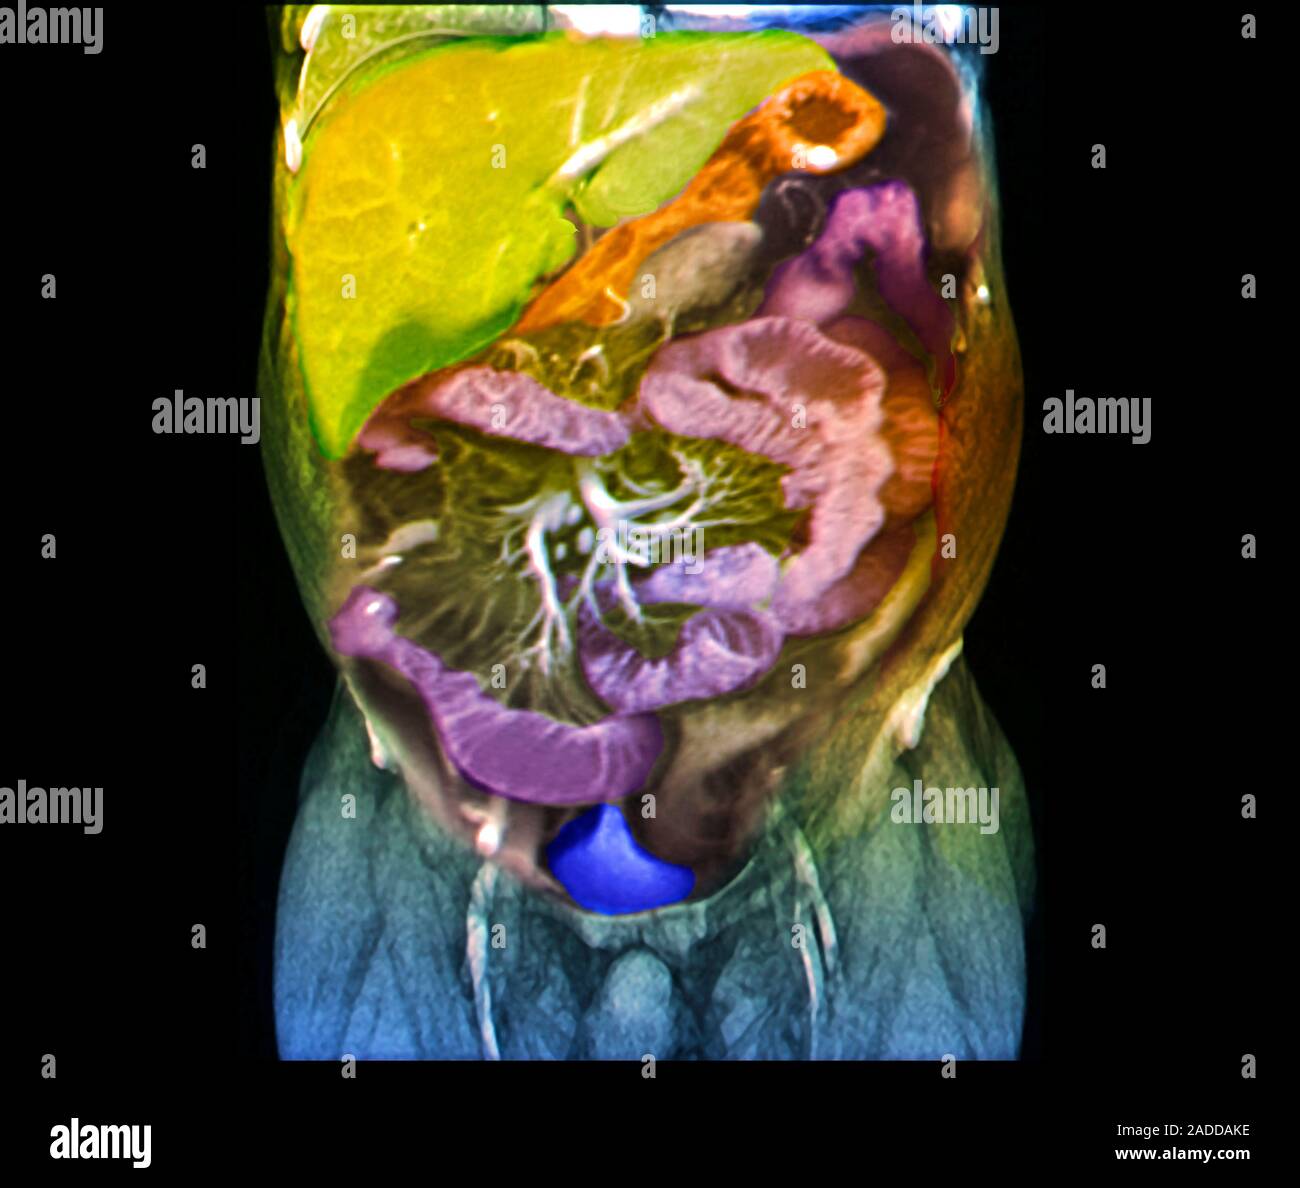

Crohn's disease research. Coloured coronal resonance imaging Can An Mri Scan Detect Crohn Disease If you show signs or symptoms of the condition, your doctor may use a variety. There’s no single diagnostic test for crohn’s disease. New and emerging roles of mri in inflammatory bowel disease. A systematic approach is presented to grade disease. In addition, mri enterography and enteroclysis has allowed detection of small bowel crohn disease, similar to that of small. Can An Mri Scan Detect Crohn Disease.